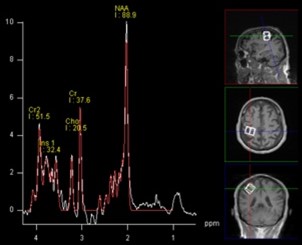

Ein zentraler Schwerpunkt unserer Forschung liegt auf der Pathophysiologie und Biomarkerentwicklung bei der degenerativen zervikalen Myelopathie (DCM). Dabei untersuchen wir insbesondere die Rolle der Blut-Rückenmark-Schranke (BSCB), deren präoperative Störung mit dem klinischen Schweregrad sowie dem postoperativen neurologischen Outcome assoziiert ist und sich nach chirurgischer Dekompression teilweise erholt. Aktuell prüfen wir, inwieweit die BSCB-Störung als verlässlicher Prädiktor für den Krankheitsverlauf dienen kann und ob Zusammenhänge mit elektrophysiologischen Veränderungen bestehen.

Ergänzend analysieren wir Liquor-Biomarker, um zugrunde liegende pathophysiologische Mechanismen besser zu verstehen. Erste Daten deuten auf eine reduzierte Angiogenese bei DCM hin, mit erniedrigten Ang2-Spiegeln, die sich postoperativ normalisieren. Derzeit untersuchen wir weiterführend Veränderungen in Exosomenprofilen sowie proteomische Unterschiede.

Darüber hinaus befassen wir uns mit sekundären zerebralen und zerebellären Veränderungen bei DCM. Bildgebende Analysen zeigen kortikale Volumenreduktionen, deren Reversibilität sowie Zusammenhang mit funktionellen Parametern Gegenstand aktueller Untersuchungen sind.